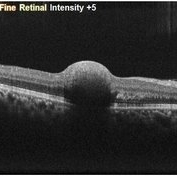

Sub-Internal Limiting Membrane Hemorrhage

Apr 17 2025 by Malvika Singh

OCT of a 41 year-old, male, with a central retinal vein occlusion and a foveal sub-internal limiting membrane hemorrhage.

Photographer: Dr Malvika Singh, Retina Foundation, Ahmedabad, India

Imaging device: Mirante SLO/OCT

Condition/keywords: optical coherence tomography (OCT), SUB ILM hemorrhage